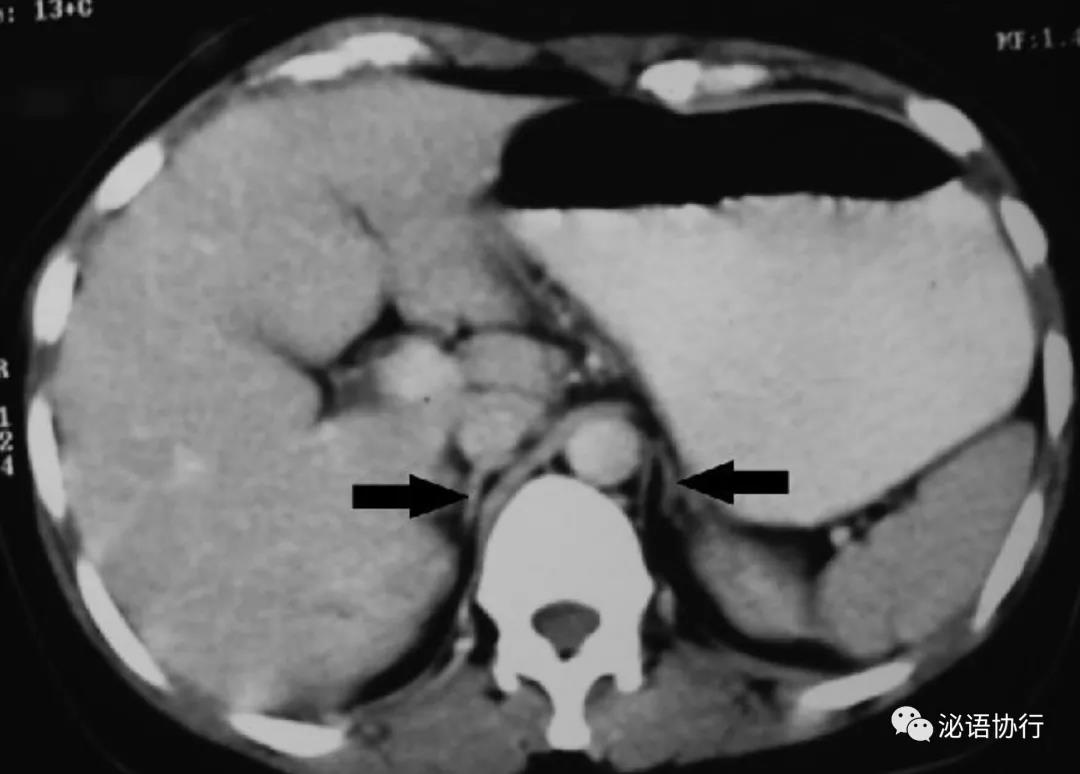

(1)肾上腺本身的损害:常见于自身免疫性疾病、结核、AIDS等。自身免疫性疾病是指机体产生了攻击自身肾上腺皮质的抗体会导致肾上腺萎缩(图2),发达国家中80%的原发性肾上腺功能减退症是此种病因,而在中国更需要关注结核导致肾上腺皮质功能减退。其他少见病因有肾上腺脑白质营养不良、转移性肿瘤。

图2:自身免疫性肾上腺炎CT图像提示肾上腺萎缩